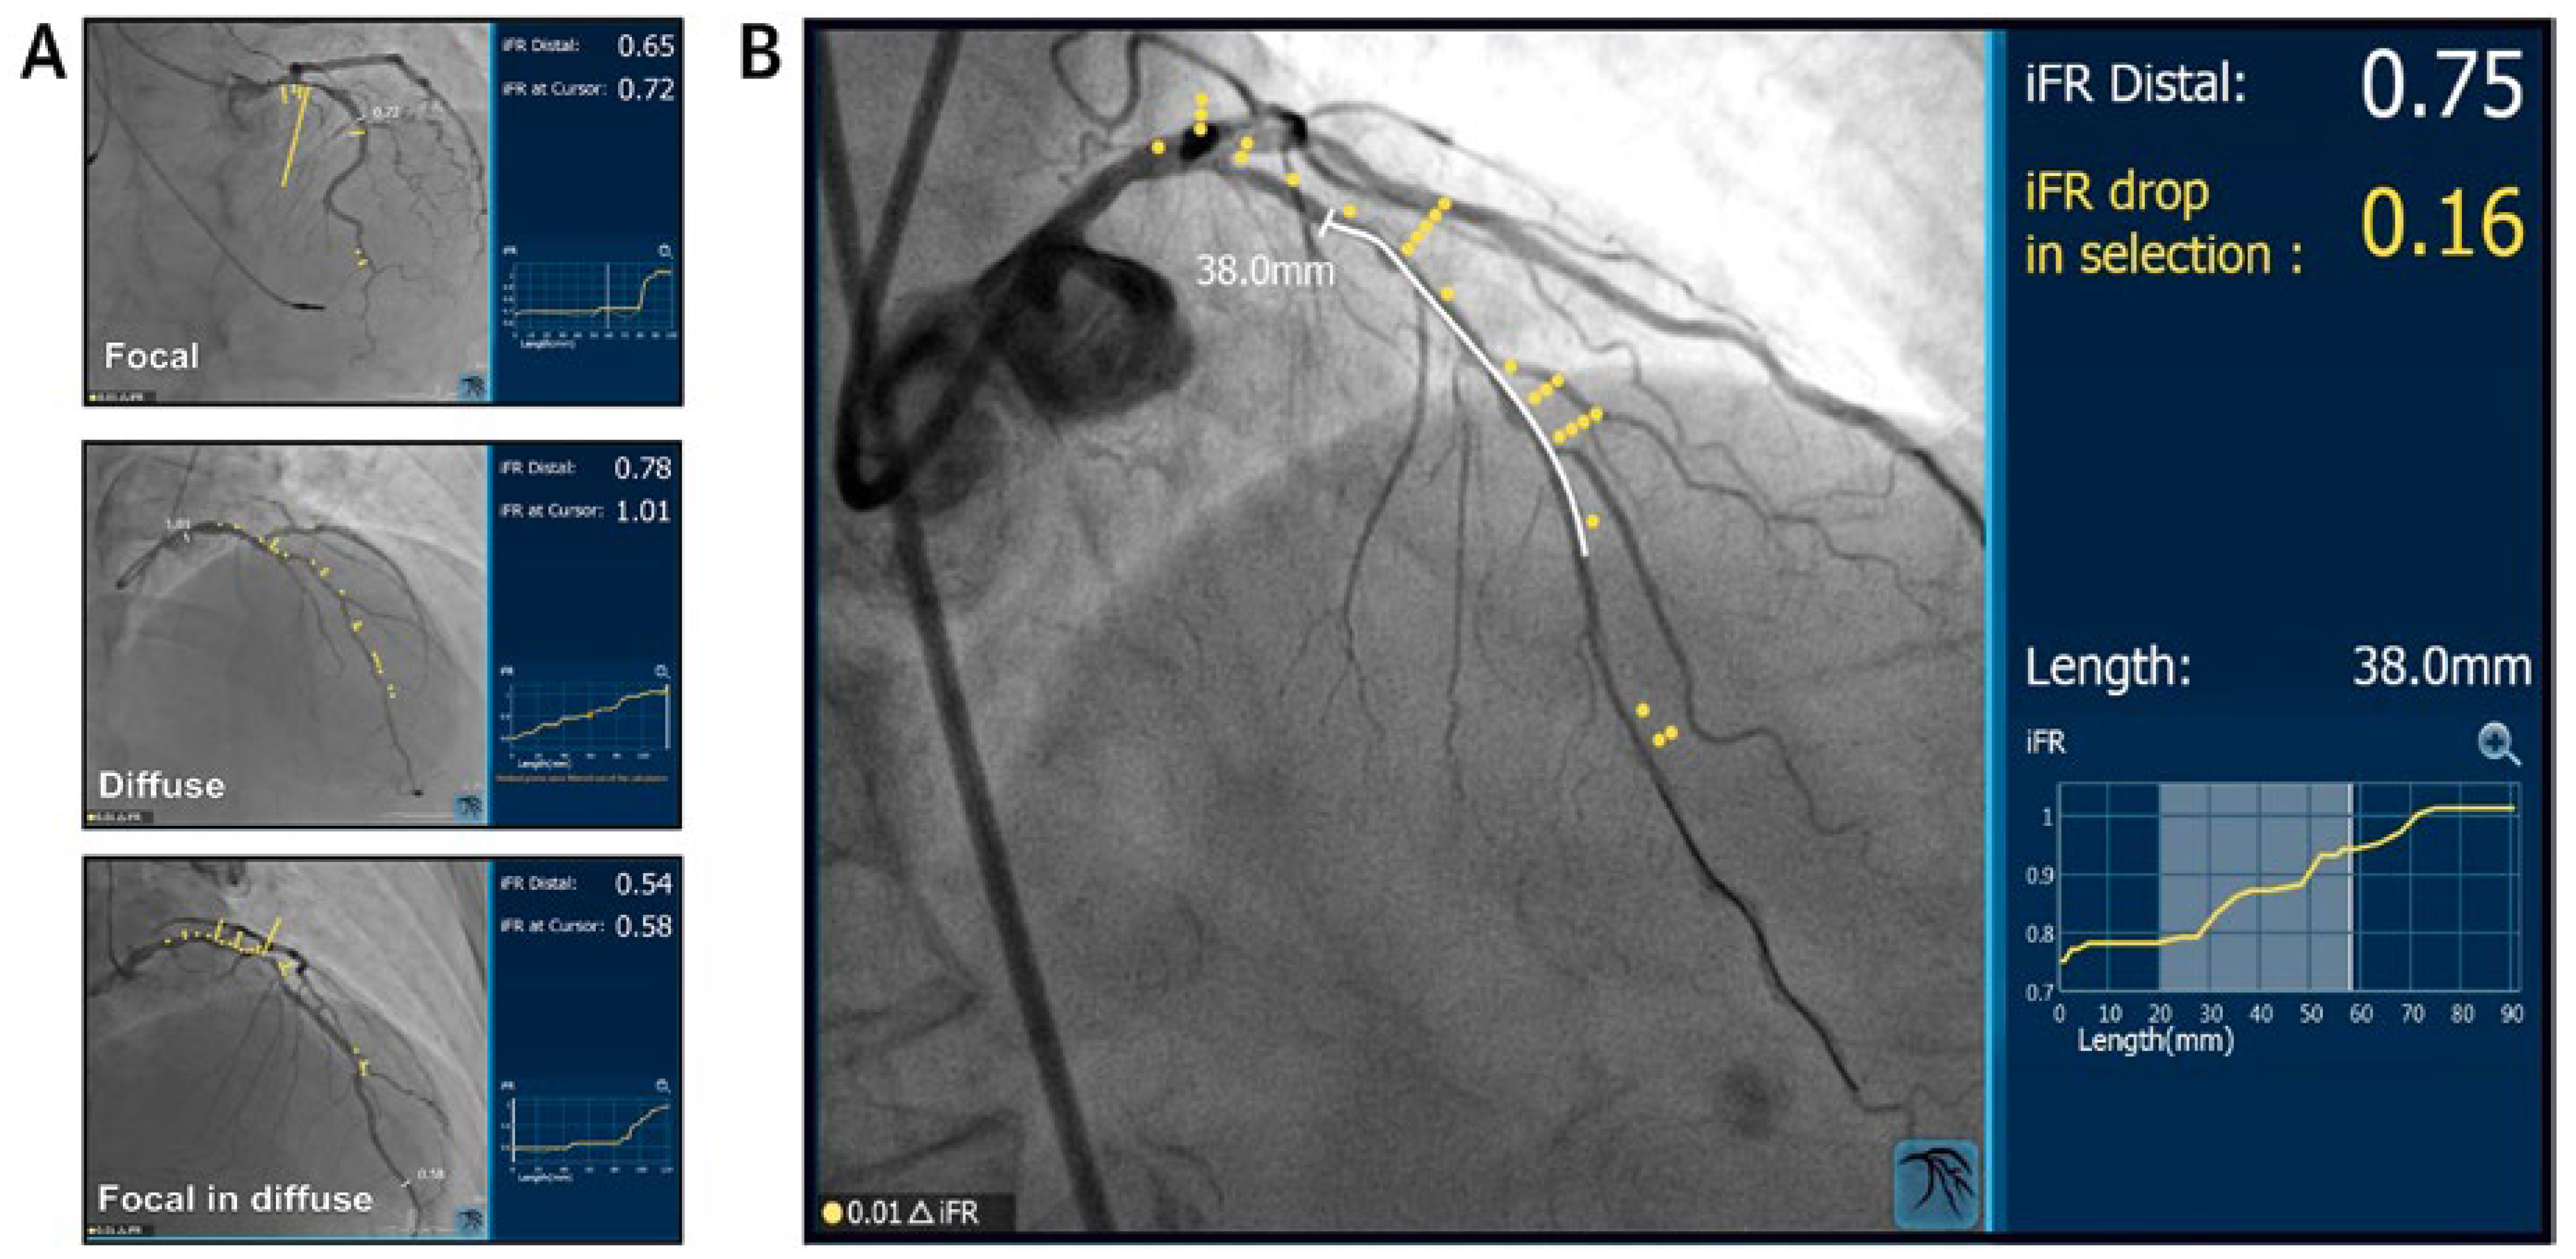

iFR pullback

iFR co-registration

- Nijjer, S.S.; Sen, S.; Petraco, R.; Mayet, J.; Francis, D.P.; Davies, J.E.R. The Instantaneous wave-Free Ratio (iFR) pullback: A novel innovation using baseline physiology to optimise coronary angioplasty in tandem lesions. Cardiovasc Revascularization Med 2015, 16, 167–171. [Google Scholar] [CrossRef]

- Nijjer, S.S.; Sen, S.; Petraco, R.; Escaned, J.; Echavarria-Pinto, M.; Broyd, C.; et al. Pre-angioplasty instantaneous wave-free ratio pullback provides virtual intervention and predicts hemodynamic outcome for serial lesions and diffuse coronary artery disease. JACC Cardiovasc Interv 2014, 7, 1386–1396. [Google Scholar] [CrossRef]